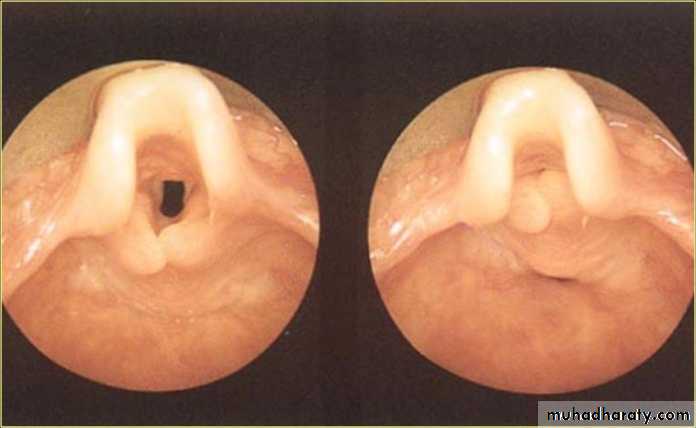

On Exam.

The diagnosis is made at endoscopy with the child breathing spontaneously.Classical appearance include an omega-shaped epiglottis, short aryepiglottic folds and loose redundant mucosa over the arytenoids.

On inspiration, the cartilages are sucked inwards obstructing the airway.